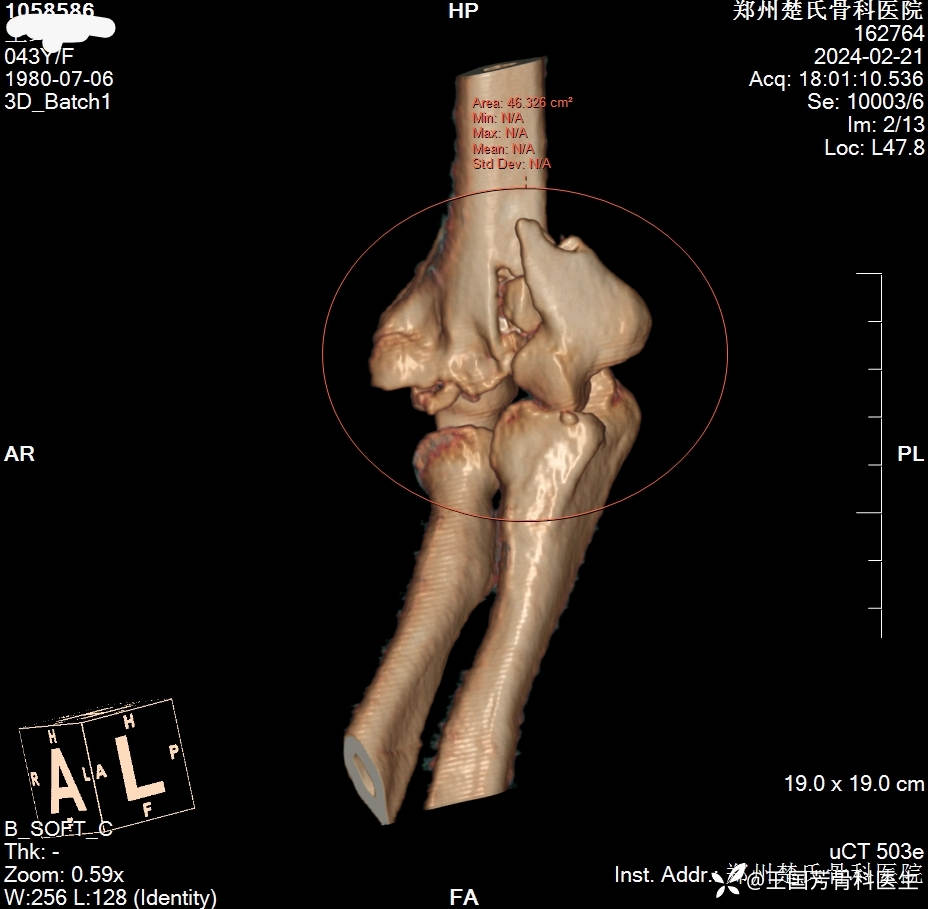

女,43岁,摔倒致右肘肿痛伴活动受限2小时入院。

诊断:肱骨髁间粉碎性骨折

伸直型损伤

Radjn分型:IV型